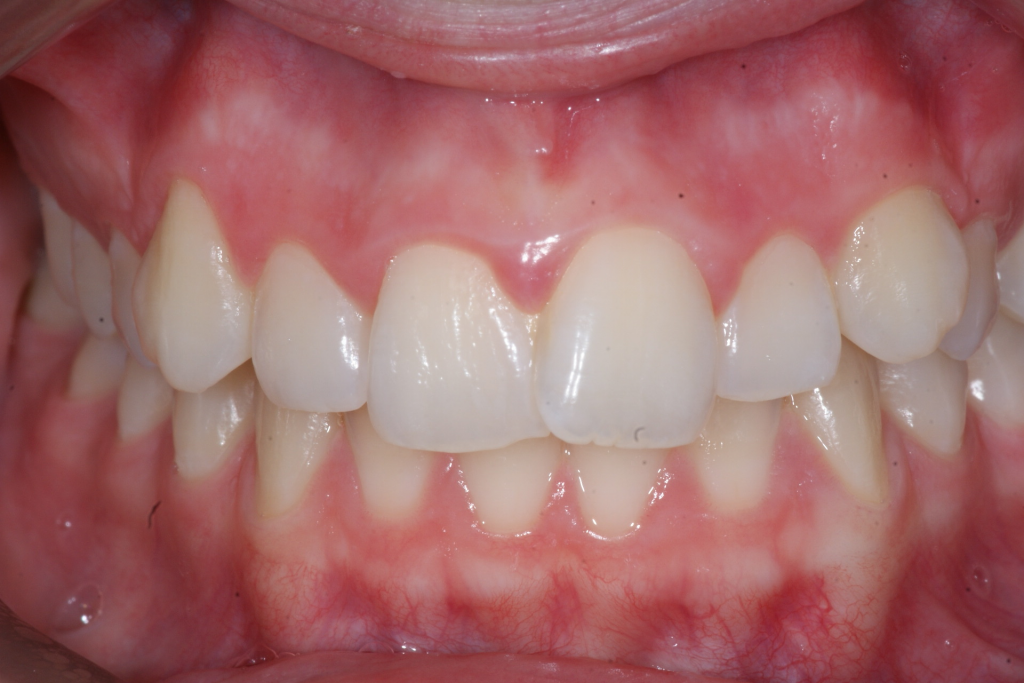

Correction d’une malocclusion de type Classe II division 1, surplomb horizontal inadéquat et chevauchement modéré aux 2 arcades. Des appareils fixes (broches et vis d’expansion) et des élastiques furent nécessaires pour améliorer ce sourire. Traitement chez une adolescente, réalisé en 18 mois.